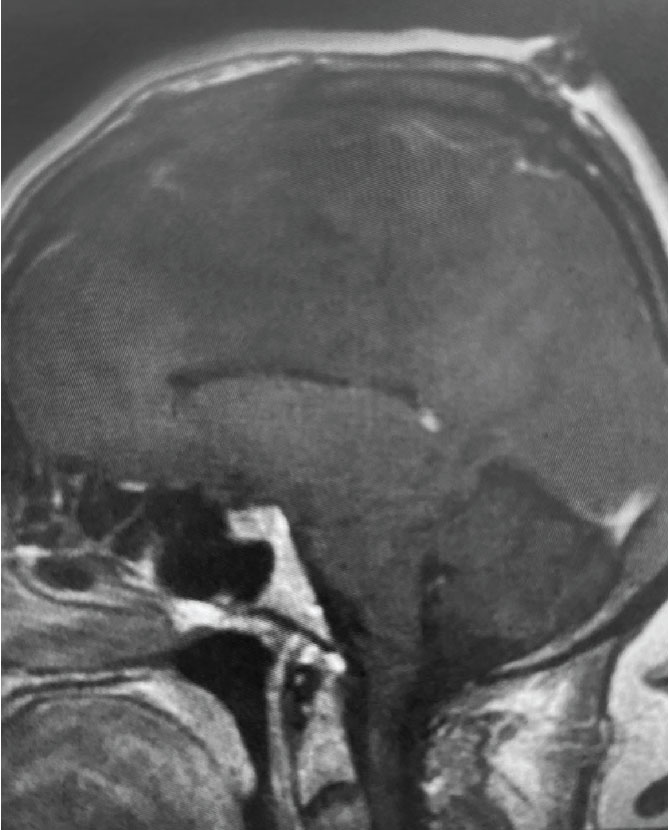

Fig 1. B) Pre-operative, sagittal post-contrast MRI.

This is a 55 year old right-handed woman who was having progressive balance problems. MRI with and without contrast demonstrated a 7 cm partly cystic meningioma involving the left frontal convexity and falx, and encasing the superior sagittal sinus. There was also tumor involvement of part of the convexity skull.

Meningiomas that involve the superior sagittal sinus: Sometimes convexity or falx meningiomas will grow into the superior sagittal sinus. Sometimes the sinus can become completely occluded. Usually this occurs over many years, and as such, the brain has time to develop venous collaterals. So, while in a normal person, sudden occlusion of the superior sagittal sinus could lead to venous infarction or death, the very gradual occlusion that can be seen with meningiomas, does not lead to these problems. Also, if the sinus is filled with tumor and completely occluded, it can usually be safely removed at that segment.

Fig 1. A) Pre-operative, post-contrast, coronal MRI. Arrow points to tumor involvement in the superior sagittal sinus.